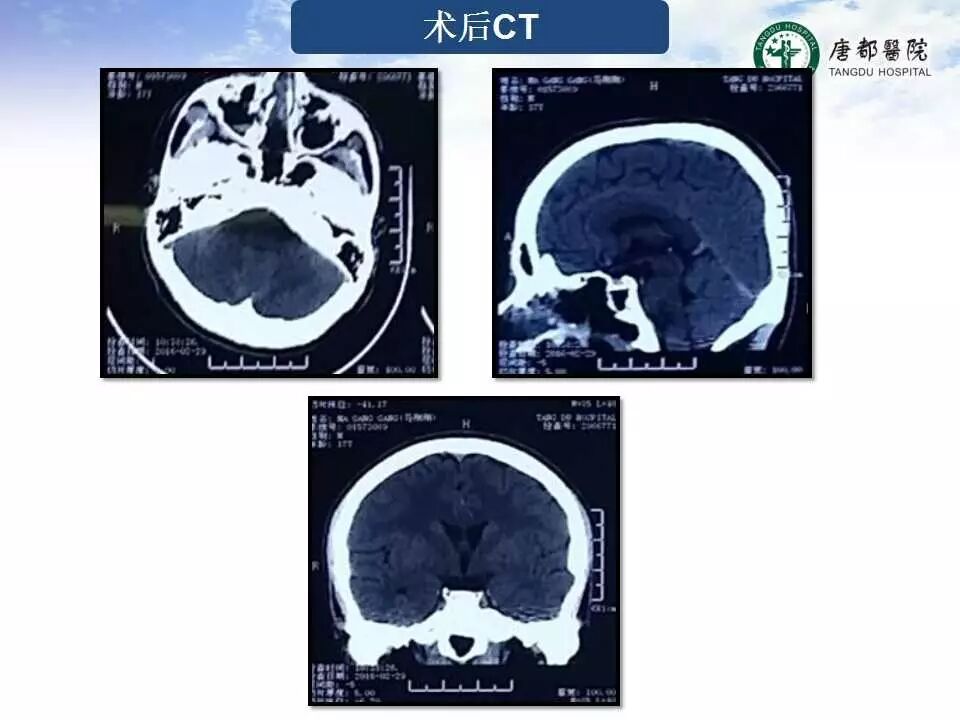

Case 1

长按并识别二维码即可查看该手术视频